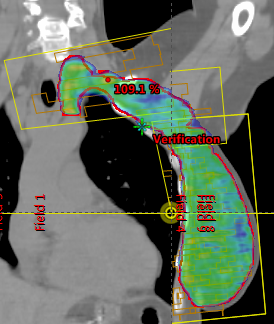

Target: PTV_TOT_EVAL

Dose prescription: 50.0 Gy in 25 fr.

Protocol followed: RTOG-1304 ( Criteria squeezed more ! )

Techniques: 3D-CRT, IMRT, VMAT

Dose calculation grid should be less than 3 mm